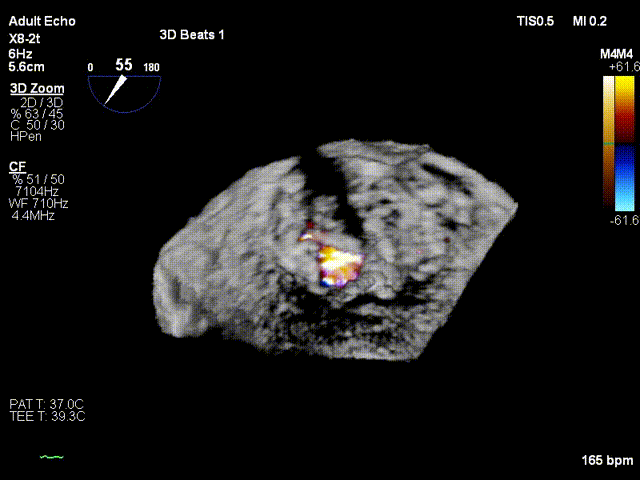

考虑患者残余反流仍偏高,经团队评估后,遂植入第二个夹子。术后即刻(植入第二个夹子)TEE示:二尖瓣反流降低至微量,二尖瓣压差1mmHg;测定左房压力:19/16/14mmHg,手术成功。患者术后即刻麻醉清醒,血压维持在110/60mmHg, 胸闷,呼吸困难症状明显缓解。

3D基线view

3D一个架子后

3D Final